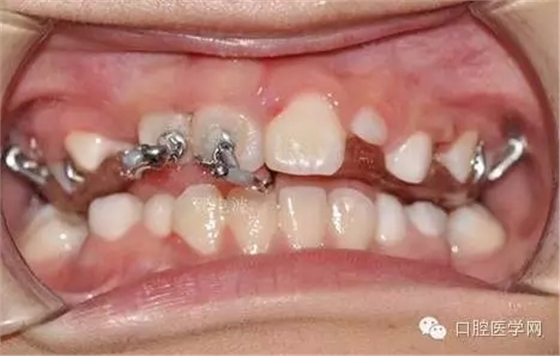

鏈狀正畸牽引裝置粘固后的口內情況

這個鏈式的超級好用,大力推薦。質量很好避免了結扎絲容易斷,托槽粘結不牢的弊端。(寫到這個地方不得不聊個小橋段,上次去上海咱會淘到的這個鏈式固定裝置,本來小美女說是40元一個,結果我說俺常做埋伏牙,要給人家做做宣傳,10元一個就給我試用了。40元給我4個,當時那叫一個感動呀,。。感謝生命中遇見了你。。。